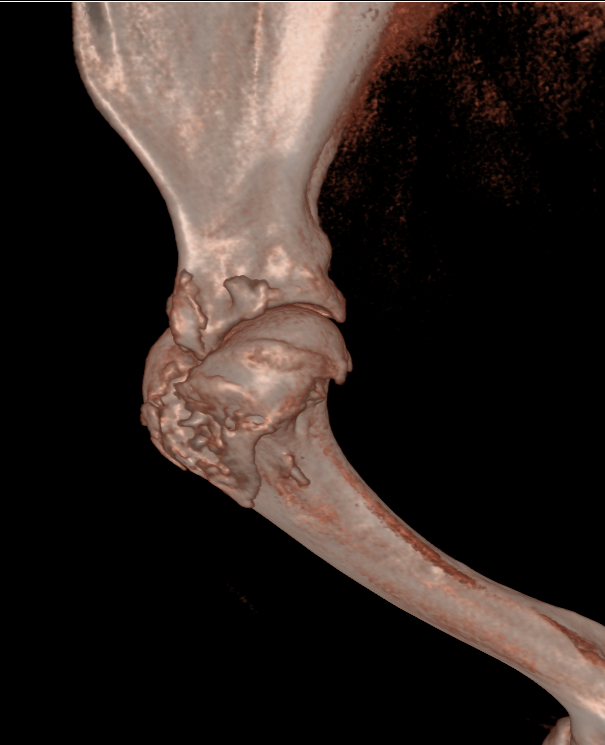

keeshond van 5 maanden met een  ernstige patella luxatie . De knieschijf zit permanent aan de binnenzijde van de knie. Het onderbeen heeft een torsie van 58.1 graden ten opzichte van het bovenbeen. Het bovenbeen heeft een kanteling van 29 graden ten opzichte van het kniegewricht.

De scan beelden zijn gebruikt om een operatieve ingreep voor te bereiden.